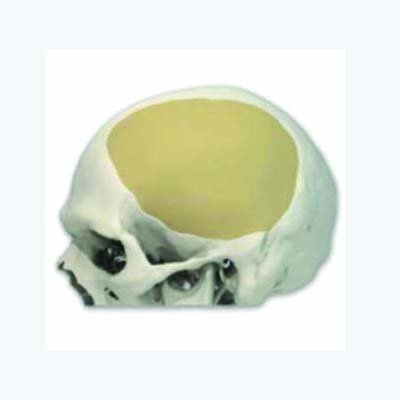

Medicad Implants is a state of the art technology firm specialized in providing customized solutions for hard tissue replacement and cranial implant in India. We are a synergy of motivated and experienced Engineers, Medical Practitioners and Designers striving to help surgeons for cranial implant india for their patients.

Patient specific” Technology is one of the latest development in the medical field aimed at providing more accurate and lasting healthcare to patients. It synergically ties the medical imaging techniques with reverse engineering and rapid manufacturing concepts long being used in Aerospace and automobile fields to provide a unique solution on a case by case basis.